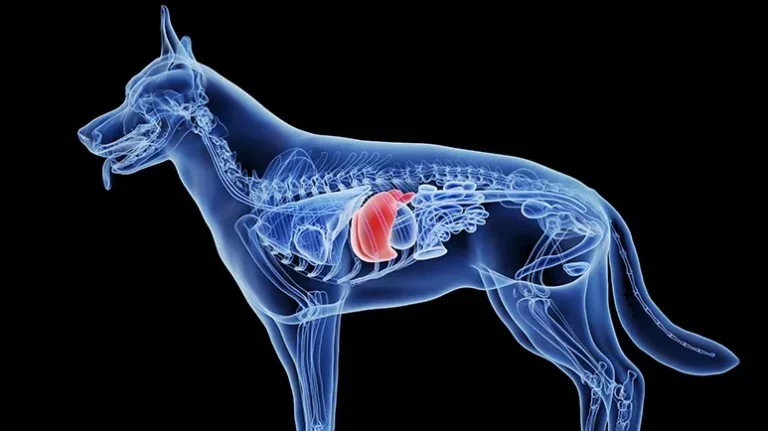

If copper levels are too low, it can lead to issues like anemia, a dull coat, or weaker bones. This may occur occurs when higher than normal levels of other minerals make it harder for the body to absorb copper.1 However, when copper levels are too high, they can cause even more of a problem. Once copper is absorbed from food, it travels to the liver, where it is processed, stored, and eliminated as needed. Think of your dog’s liver like a water filter — it catches copper and flushes the extra out. Problems begin when that system breaks down.

Copper storage disease, also called copper-associated hepatopathy, is a condition where the liver cannot clear excess copper properly. Instead of being excreted, the copper, it builds up inside liver cells. Over time, this buildup can trigger inflammation, which can gradually damage liver tissue.2

Copper storage disease is more commonly seen in dogs than in cats, but humans can develop a similar condition as well. In dogs, it’s most commonly due to genetics — which means inherited genes that abnormally affect how copper is metabolized.3 Diet or ongoing liver strain may also contribute to the development of this disease.

Blood tests can point to a problem with your pet’s liver, but they alone cannot confirm copper storage disease. To know for sure, veterinarians usually need a liver biopsy, which involves collecting a small sample of liver tissue to assess it for copper storage disease.

A biopsy can sound scary, but the procedure is often quick, performed under sedation, and most dogs recover well. It gives your vet the clearest answers and confirms the diagnosis, making it possible to build a treatment plan tailored to your dog’s needs.